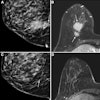

Another article drawing attention in our Women's Imaging Community featured new research comparing an abbreviated breast MRI protocol with standard breast MRI and contrast-enhanced mammography (CEM) in supplemental breast cancer screening. Although abbreviated MRI performed comparably to standard breast MRI, CEM showed some benefits as well as drawbacks.